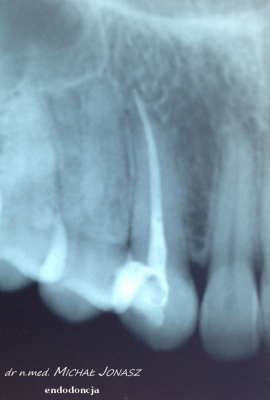

Zmiany okołowierzchołkowe to ogniska zniszczenia kości wokół wierzchołków korzeni zębów. Przewlekłe, nieleczone zmiany zapalne w obrębie korzeni zęba mogą powodować duże uszkodzenia kości i skutkować utratą zębów. Reendo polega na usunięciu materiału, którym wypełnione są kanały i zlokalizowaniu nieprawidłowości, czyli niedostatecznie oczyszczonego lub wypełnionego kanału albo pozostawionego, złamanego narzędzia w jego świetle. Dzięki mikroskopowi problemy anatomiczne, takie jak wąskie, zarośnięte kanały, zakrzywione korzenie, boczne, nietypowe odnogi są możliwe do wyeliminowania.

Diagnostyka obrazowa i wprawne oko Stomatologa są podstawą do podjęcia powtórnego leczenia kanałowego. Wychwycenie zmian patologicznych kierujących na powtórne leczenie kanałowe często jest efektem wnikliwej analizy zdjęć RTG. Powtórnego leczenia kanałowego wymagają zęby, których kanały korzeniowe nie zostały prawidłowo wypełnione. Im dłuższy czas upływa od zakończenia pierwotnego leczenia kanałowego, tym mniejsza szansa, że ząb da o sobie ponownie znać. Nieprawidłowo przeleczony kanałowo ząb, to potencjalnie ogromne ryzyko dla pacjenta. Ząb źle leczony kanałowo przypomina o sobie po wielu latach, bądź w postaci dolegliwości bólowych, bądź przez wolno, bezobjawowo rozwijającą się torbiel. Wytworzenie się torbieli wymaga już interwencji z zakresu chirurgii stomatologicznej. W takiej sytuacji po leczeniu powtórnym pacjent jest kierowany do chirurga na zabieg wyłuszczenia torbieli.

Na zdjęciu RTG efekt leczenia endodontycznego można ocenić po 3 – 6 miesiącach. Każde kanałowe leczenie należy systematycznie kontrolować poprzez wykonywanie rutynowych zdjęć radiologicznych, tak by zawczasu uniknąć nieprzyjemnych problemów.